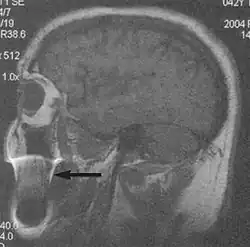

Metal artifacts occur at interfaces of tissues with different magnetic susceptibilities, which cause local magnetic fields to distort the external magnetic field. This distortion changes the precession frequency in the tissue leading to spatial mismapping of information. The degree of distortion depends on the type of metal (stainless steel having a greater distorting effect than titanium alloy), the type of interface (most striking effect at soft tissue-metal interfaces), pulse sequence and imaging parameters. Metal artifacts are caused by external ferromagnetics such as cobalt containing make-up, internal ferromagnetics such as surgical clips, spinal hardware and other orthopaedic devices, and in some cases, metallic objects swallowed by people with pica.[3] Manifestation of these artifacts is variable, including total signal loss, peripheral high signal and image distortion (Figs 3 and 4).[1] Reduction of these artifacts can be attempted by orientating the long axis of an implant or device parallel to the long axis of the external magnetic field, possible with mobile extremity imaging and an open magnet. Further methods used are choosing the appropriate frequency encoding direction, since metal artifacts are most pronounced in this direction, using smaller voxel sizes, fast imaging sequences, increased readout bandwidth and avoiding gradient-echo imaging when metal is present. A technique called MARS (metal artifact reduction sequence) applies an additional gradient, along the slice select gradient at the time the frequency encoding gradient is applied.